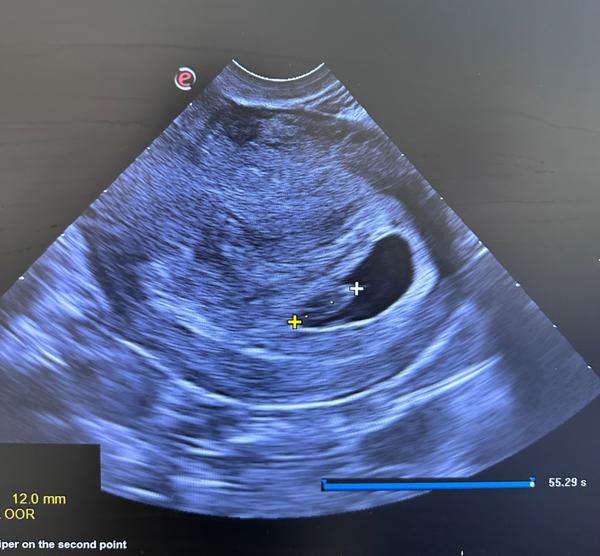

Zväčšený žĺtkový vak v 8. týždni. Má niekto pozitívnu skúsenosť?

Bola som na prvé kontrole u gynekológa 7tt+4

Akcia ❤️ bola prítomná, maternica že nasiaknutá už , plod zodpovedá veľkosti v danom dni a týždni

Jedine čo poznamenala že je zväčšený zltkovy vak no nemerala ho na nič ma neupozornila

@mony970 ahoj pošlem ti fotku môjho sona 7+3 pre predstavu . Podľa mňa keby to bolo zle tak by ti to hneď povedala 🙂 🫶🏻